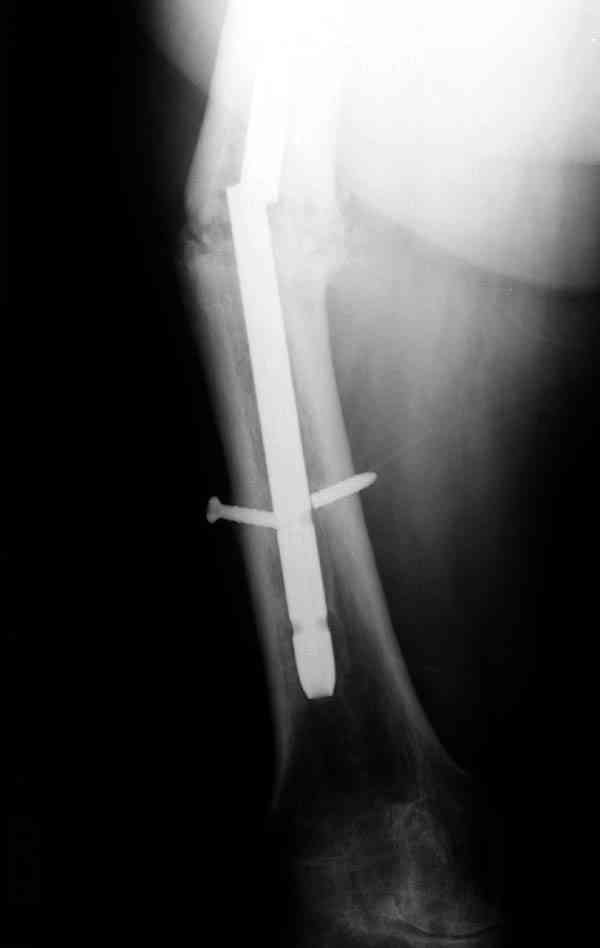

Уважаемые коллеги! У пациента 50-ти лет ложный сустав голени, перелом интрамедуллярного штифта. Перелому около 2 лет, ходить с полной нагрузкой начал через 3 мес. после операции. Боли при ходьбе почувствовал около 2 мес. назад. На данный момент ходит с полной нагрузкой без посторонней опоры. Среди коллег развернулась дискуссия по поводу способа оперативного лечения: -удаление штифта с перештифтовыванием блокированным штифтом с рассверливанием и остеотомией м\б кости -стабилизация зоны ложного сустава по медиальной поверхности LCP-пластиной с декортикацией или без -удаление штифта или без и синтез в АВФ с декотрикацией или без и остеотомией м\б кости

уважаемый коллега! Здесь имеется типичный тугой ложный сустав б/берцовой кости. У нас бы удалили старый стержень, реостеосинтез более толстым стержнем с рассверливанием с блокированием в динамическом варианте. Проблема будет с удалением дистального отломка стержня. Здесь на форуме это вопрос уже рассматривался неоднократно. Поищите по поисковику.Вот здесь, кажется http://weborto.net/forum/1164105478/, http://weborto.net/forum/1192794837

Все перечисленные варианты способны привести к желаемому результату. Несращение здесь - результат нестабильности, так что любой вариант

стабилизации решит проблему. Одного безоговорочно лучшего нет, у всех есть плюсы-минусы.

Наиболее быстро достичь опорности без боли и внешних приспособлений - удаление и блокируемый реостеосинтез с рассверливанием. Лучше бы тоже с

восстановлением оси (отклоняющая спица в дистальном отломке, чтобы новый стержень прошел не в старый канал, а кзади от него), еще и для создания дополнительного напряжения тканей в области несращения. Открывать зону несращения не надо.

Периферический отломок стержня - наверно, надо воспользоваться отверстием, над ним сделать трепанацию и через него вверх провести длинную спицу, сделав на ее нижнем конце крючок. Лучше уже перед этим рассверлить центральный отломок.

Сросшаяся малоберцовая как распорка привела к образованию ложного сустава. В таких случаях удаляем сломанный штифт и проводим стимуляцию ложного сустава рассверливанием. Рассверливание канала создает стимуляцию на месте ложного сустава, и динамический вариант блокировки штифта с большим диаметром создаст стабильность. Ранняя нагрузка после остеотомии малоберцовой приведет к сращению ложного сустава.

Приспособление для удаления сломанных штифтов и наличие ЭОП облегчит задачу. При отсутствии крючка тогда можно применить обычный длинный ball pointed guide wire от интрамедулярного набора. Проволока, пропущенная за пределы гвоздя и зажатая другая вытащат сломанный конец штифта без проблем.